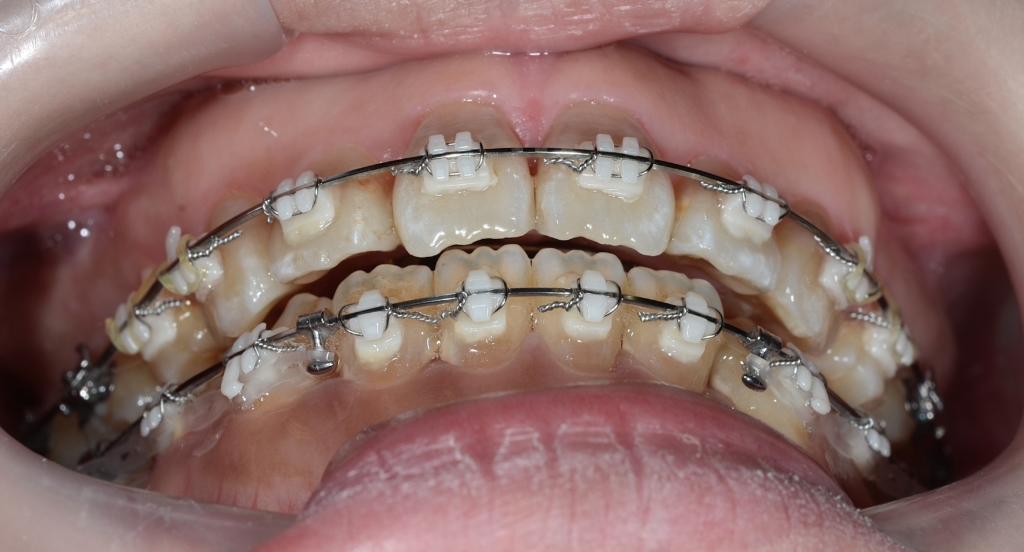

前歯のガタガタ(叢生)を解消してきれいに並べて、できるだけ引っ込めたのですが、元々の噛み合わせが上顎前突であったため、どうしても出っ歯が残ってしまいました。

単純に歯並びと噛み合わせを治すだけなら、やりようはあったのですが、できるだけ口元も引っ込めてあげたい!という願いがあったので、引っ込められる分引っ込めて足りない分は後で歯並びごとプラスアルファ―引っ込めよう!という作戦で進めています。

予定通り上顎の口蓋にアンカースクリューを植立しました。

あらためて上顎に、「PLAS」と「パラタルバー」を装着して、上の歯列全体を後方へ押して引っ込めて行きます。